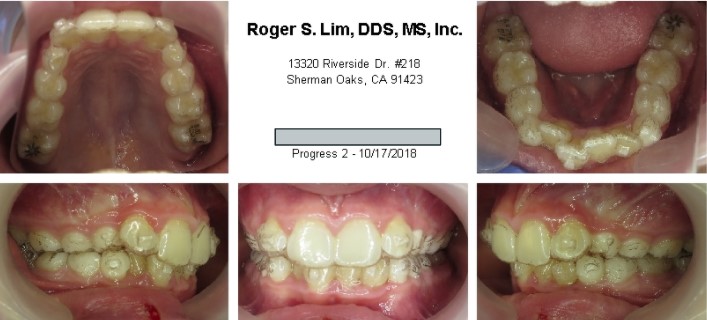

Posterior crossbite before Expander

Posterior crossbite after Expander